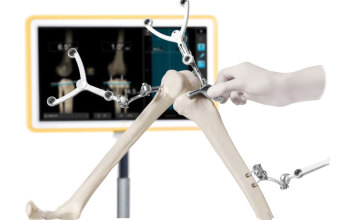

Τα συστήματα CONTOUR®NEXT αποτελούν τον ιδανικό σύμμαχο κάθε ατόμου με διαβήτη αλλά και των επαγγελματιών υγείας που τα υποστηρίζουν